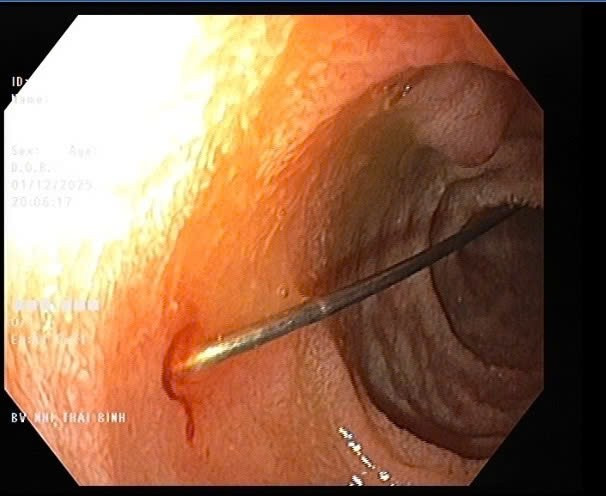

Thủ thuật nội soi cho thấy rõ hơn hình ảnh dị vật kim may dài 4cm - Ảnh BVCC

Hình ảnh nội soi quan sát thấy niêm mạc thực quản và dạ dày của trẻ không viêm loét; tại hành tá tràng D1–D2 phát hiện dị vật kim may dài 4cm, một đầu nhọn cắm vào thành tá tràng, một đầu nhựa tròn hình cúc đang nằm trong lòng ruột.

Ê- kíp đã sử dụng thòng lọng chuyên dụng tiếp cận đúng vị trí và gắp dị vật ra ngoài an toàn. Thủ thuật diễn ra thuận lợi, không gây trầy xước, không có biến chứng chảy máu sau gắp dị vật.